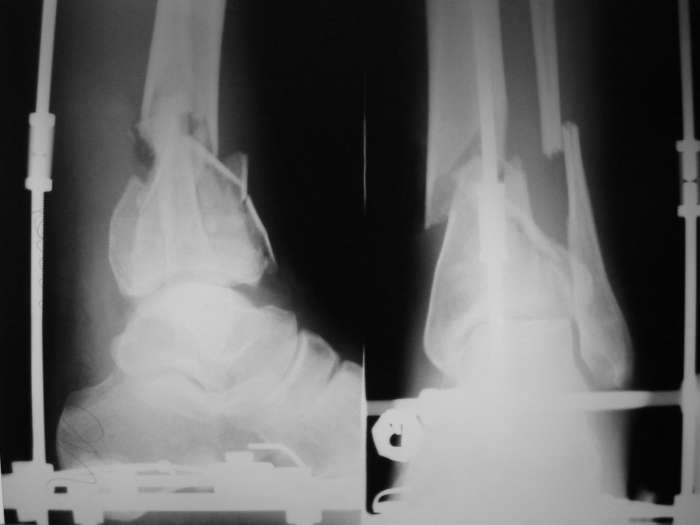

Здравствуйте, коллеги. Пять дней назад поступил молодой человек с DS: открытый внутрисуставной многооскольчатый перелом дистального метафиза правой б/берцовой кости, надсиндесмозный поперечный перелом м/берцовой кости со смещением. Нагноение раны.

Наложен АВФ, на снимке результат сразу после операции и устранения "холостого хода". Ведется постепенная дистракция. Этапных снимков не проводил, т.к. по отломкам в ране можно ориентироваться в степени репозиции. Получает а/б по результату посева и антибиотикограммы отделяемого из раны.

Учитывая общеизвестный "дефицит" мягких тканей голени, смущает размер кожного дефекта. Отек и воспаление значительно меньше. Купированы явления лимфангоита. Температура в норме. Хотелось бы услышать мнение о дальнейшей тактике ведения такого больного. Чем "прикрыть" рану? Дожидаться ли роста грануляций с последующей пластикой расщепленным лоскутом или ....?

Что сделано не так (требуется ли перекомпоновка АВФ для более рационального эффекта репозиции)?